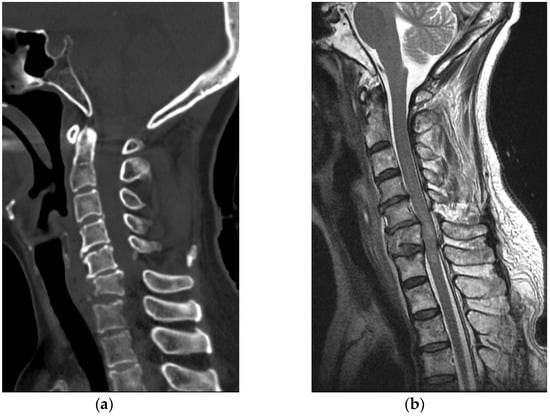

A 50-year-old healthy woman without any relevant medical history went to a nearby park with public outdoor exercise equipment on the morning of 19 October 2019. The patient had been previously active and well before the accident. The patient was working out with the public exercise equipment. While hanging on the inversion table upside down, she slipped and hit her head on the ground. Thereafter, she collapsed and immediately experienced a total loss of motor power in her whole body; she was found at the park and directly transferred to our hospital by ambulance. Computed tomography (CT) brain scan results did not reveal any abnormalities. Cervical spine CT scan showed a bilateral facet dislocation on C5-6 and anterior displacement of the C5 vertebral body (Figure 4a). Cervical spine magnetic resonance imaging (MRI) also showed an anterior displacement of C5 on C6, a complete discoligamentous complex (DLC) injury, which was causing cord compression with extensive edematous cord signal change, and an intramedullary hemorrhage (Figure 4b).

Figure 4. (a) Cervical spine CT revealed facet dislocation at C5-C6 and anterior displacement of the C5 vertebral body; (b) Cervical spine MRI showed cord compression with edematous cord signal change and an intramedullary hemorrhage.